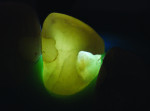

A recent development involves an innovative thin, flexible fiber-optic tip used for evaluating interproximal posterior caries (Microlux Proximal Caries Light Guide, AdDent, Inc., www.addent.com). This 0.75-mm thin light guide is also beneficial for visualizing root canal orifices within pulp chambers. For caries diagnosis, the thin light guide tip is slid into the gingival embrasure below the proximal contact under the marginal ridge. Figure 3 depicts a view from the occlusal. This method often shows caries with a higher definition than a conventional fiber-optic light guide.

Posterior teeth. Visualization of interproximal caries for posterior teeth requires initial placement of the light guide at right angles on the facial surface just below the contact area. Specialized thin fiber-optic tips that can be threaded between the teeth can offer the best diagnostic view. Interproximal caries for posterior teeth should be diagnosed using a clinical examination (Figure 12), bitewing radiographs, and FOTI (Figure 13). As seen in Figure 14, definitive preparation and caries removal verifies the accuracy of the FOTI portrayal of the caries penetration. Conventional fiber-optic tips are also valuable as an adjunctive aid when diagnosing posterior interproximal caries.